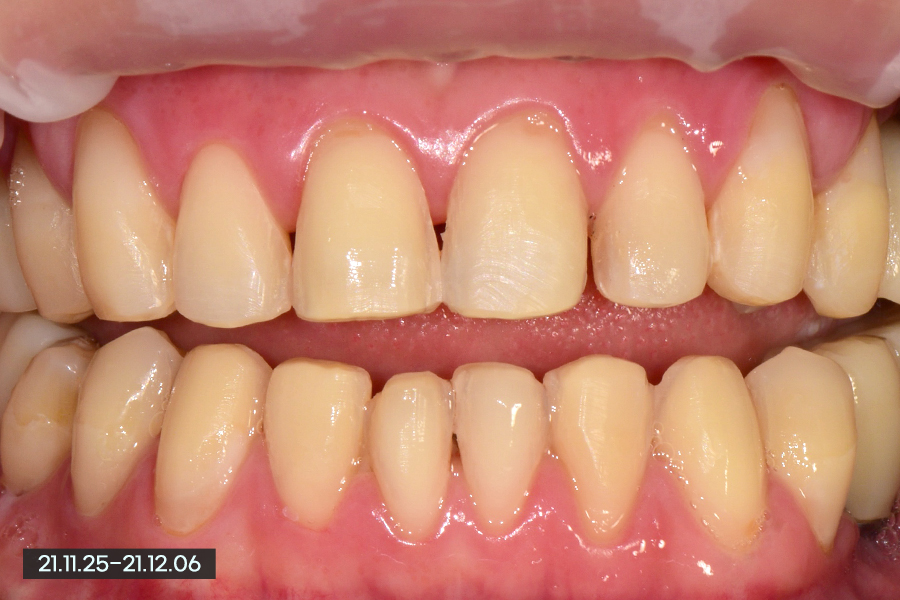

하지만 대체적으로 양호한 편이여서 최소한으로 삭제하는 최소삭제 라미네이트를 진행하기로 했는데, 환자분께서는 밝은 치아를 원하셔서 임플란트를 받은 부분을 제외하고 전부 라미네이트를 하길 원하셨습니다.

최소삭제이기 때문에 당연히 마취 없이 진행하였습니다.

치아를 다듬은 후의 사진을 보시면 아까 말씀드렸듯이 마모된 부분, 레진 변색된 부분을 제거한 후 깨끗하게 다듬었습니다. 이 상태로 스캔 또는 본을 떠서 라미네이트를 만든다고 생각하시면 됩니다.